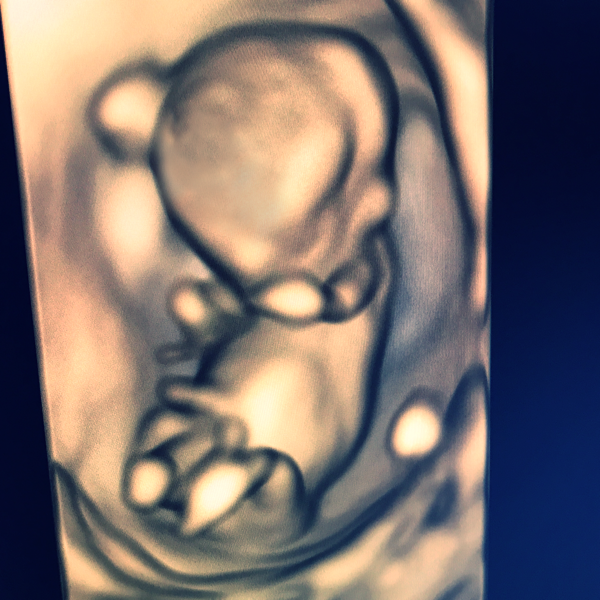

But I had a happy 12 weeks scan today - all looked good and Harmony test showed low risk for all main trisomies.

And here HE is - my second little man - me and my house full of boys!! I could not be happier after the worst 7 weeks of my life.

Oh Lh that's amazing news congratulations, a lovely little boy, such a great scan pic too.

LH what a lovely scan picture :) and good harmony results too :)

LHReturns What a lovely scan photo. So happy about your good news.